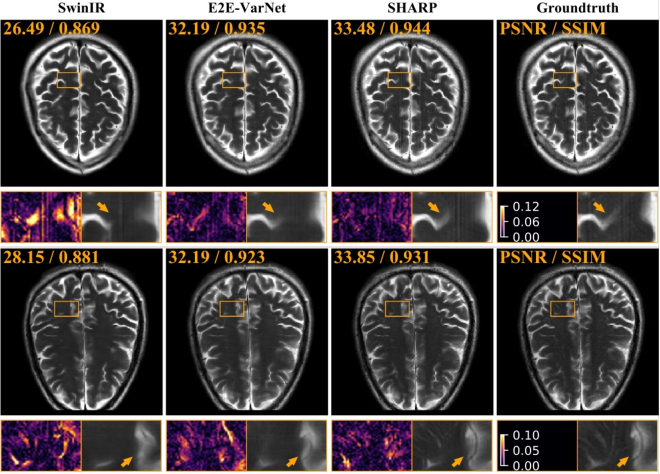

Figure 4: Visual comparison of ShaRP with several well-known methods on 2×2\times SISR. The top row shows results for SISR with gaussian blur kernel with σ=1.25𝜎1.25\sigma=1.25, while the bottom row shows results for SISR with gaussian blur kernel with σ=1.5𝜎1.5\sigma=1.5. The quantities in the top-left corner of each image provide PSNR and SSIM values for each method. The squares at the bottom of each image visualize the zoomed area in the image.

Results on SISR with deblurring prior. Figure 4 shows the visual reconstruction results for two settings with different blur kernels. As demonstrated, ShaRP successfully recovers most features and maintains high data consistency with the available measurements. Table 3 provides a quantitative comparison of ShaRP against other baseline methods, evaluated across various blur kernels and noise levels. ShaRP achieves the highest PSNR and SSIM values but ranks second in perceptual performance (LPIPS). This is consistent with the SOTA perceptual performance of DMs on SISR. However, note how the use of a deblurring prior within ShaRP enables it to recover fine details, ensuring overall competitiveness of the perceptual quality of the ShaRP solutions.